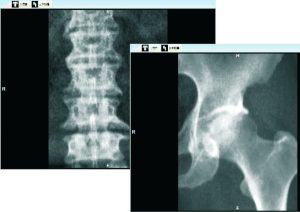

El B.S.D. DXA-600 es un densitómetro óseo basado en tecnología DEXA (Dual-Energy X-ray Absorptiometry), considerado el estándar clínico para la evaluación de densidad mineral ósea (BMD), diagnóstico de osteoporosis y análisis de composición corporal.

- Columna lumbar (AP y lateral)

- Fémur (unilateral y bilateral)

- Evaluación de cadera con análisis extendido (zonas Gruen)